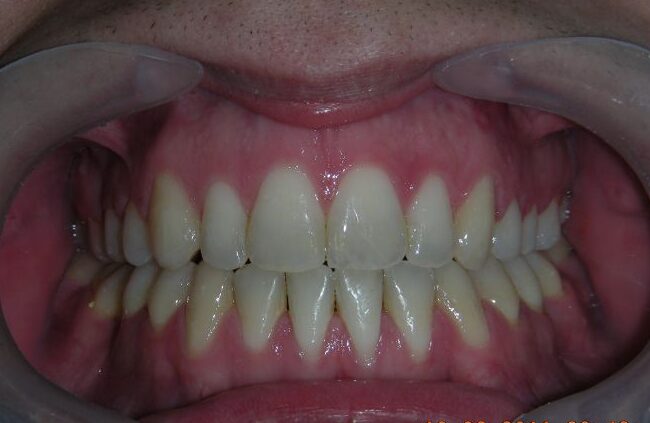

After two years of treatment using appropriate biomechanics, the overbite was successfully corrected from -8 mm to +1 mm, achieving complete closure of the anterior open bite without exacerbating the patient’s lower facial third vertical proportions. At this stage, occlusal contacts were verified using articulating paper, and functional movements of the canines and incisors were evaluated to ensure proper anterior guidance and disclusion patterns. The patient was then referred to speech therapy (myofunctional evaluation) as part of the pre-debond assessment protocol.

Finishing and Retention

At the completion of treatment (28 months) , the patient exhibited significant skeletal and dental improvements consistent with the initial treatment objectives. A reduction of 3 degrees in lower anterior facial height and a 4-degree increase in the facial axis angle were observed on post-treatment cephalometric analysis, indicating a favorable counterclockwise, anterior mandibular rotation. This skeletal change, in conjunction with the mesialization of posterior segments and space closure mechanics, led to the successful resolution of the anterior open bite. During the retention phase, a modified Hawley appliance was used in the maxillary arch, while the mandibular arch was stabilized with a fixed retainer made of twist-flex (supercable) wire #33 to #43 , which had been heat-treated to eliminate its elasticity. This retention strategy was complemented with myofunctional therapy, aimed at ensuring long-term neuromuscular stability.

The use of cephalometric measurements as quantitative indicators of skeletal and dental movement validated the biomechanical plan established from the outset of treatment. Although the patient maintains a dolichofacial biotype, the desired functional outcome—including anterior occlusal contact, vertical control, and stable mandibular positioning—was effectively achieved.